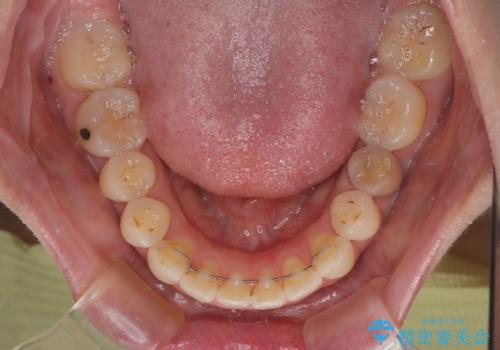

【モニター】飛び出した上顎前歯 補助装置を併用したインビザライン矯正治療

- 上下前歯が非接触となり、前方に突出していることを気にして来院された患者様です。

上下の前後差が大きいため、インビザライン単独での上顎歯列移動は困難と判断し、補助装置により上顎歯列を後方移動させ、その後インビザラインにて仕上げていくこととしました。

また、舌の突出癖が非接触の原因の大きな要因と考えられるため、舌のトレーニングをしっかり行っていくよう指導しました。

補助装置なしでも改善できる可能性はありましたが、補助装置で確実性を上げ、短期間できっちりと仕上げることができました。